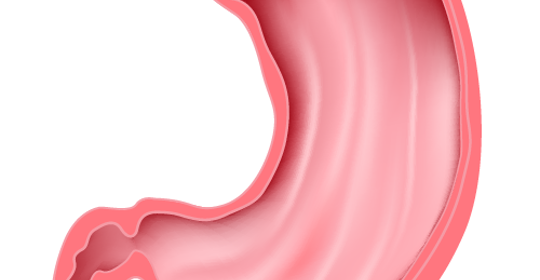

胃食道逆流患者可以吃生花生,但要注意適量。胃食道逆流是一種常見的消化系統疾病,是指胃內容物逆流至食道引起的一種症狀或併發症。

胃食道逆流患者可以吃水果,但需要適量。胃食道逆流是指胃內容物和十二指腸液等逆流入食道引起的臨床症狀及併發症。